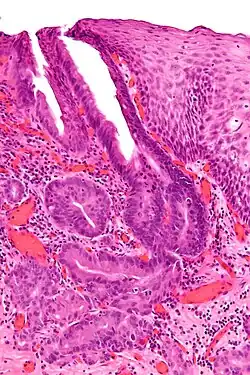

Oesophagogastric junctional adenocarcinoma

Oesophagogastric junctional adenocarcinoma (OGJ adenocarcinoma) is a cancer of the lower part of the oesophagus with a rising incidence in Western countries.[1] This disease is often linked to Barrett's oesophagus.